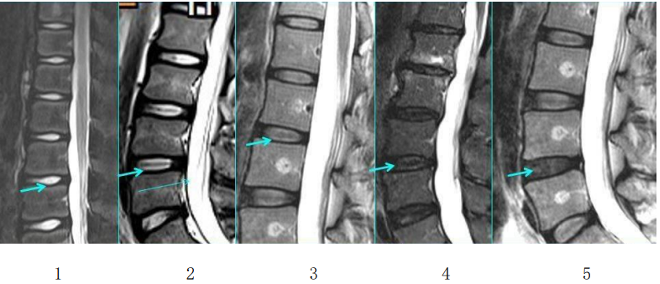

腰椎间盘突出症诊疗方案

腰椎间盘突出症诊疗方案腰椎间盘突出症中医治疗方案【定义】腰椎间盘突出症,又称腰椎间盘纤维环破裂症。成年人椎间盘发生退行性改变,使椎间盘失去原有的弹性,不能担负原来承担的压力。在过度劳损,体位骤变,猛力动作或暴力撞击下,纤维环…查看详情+